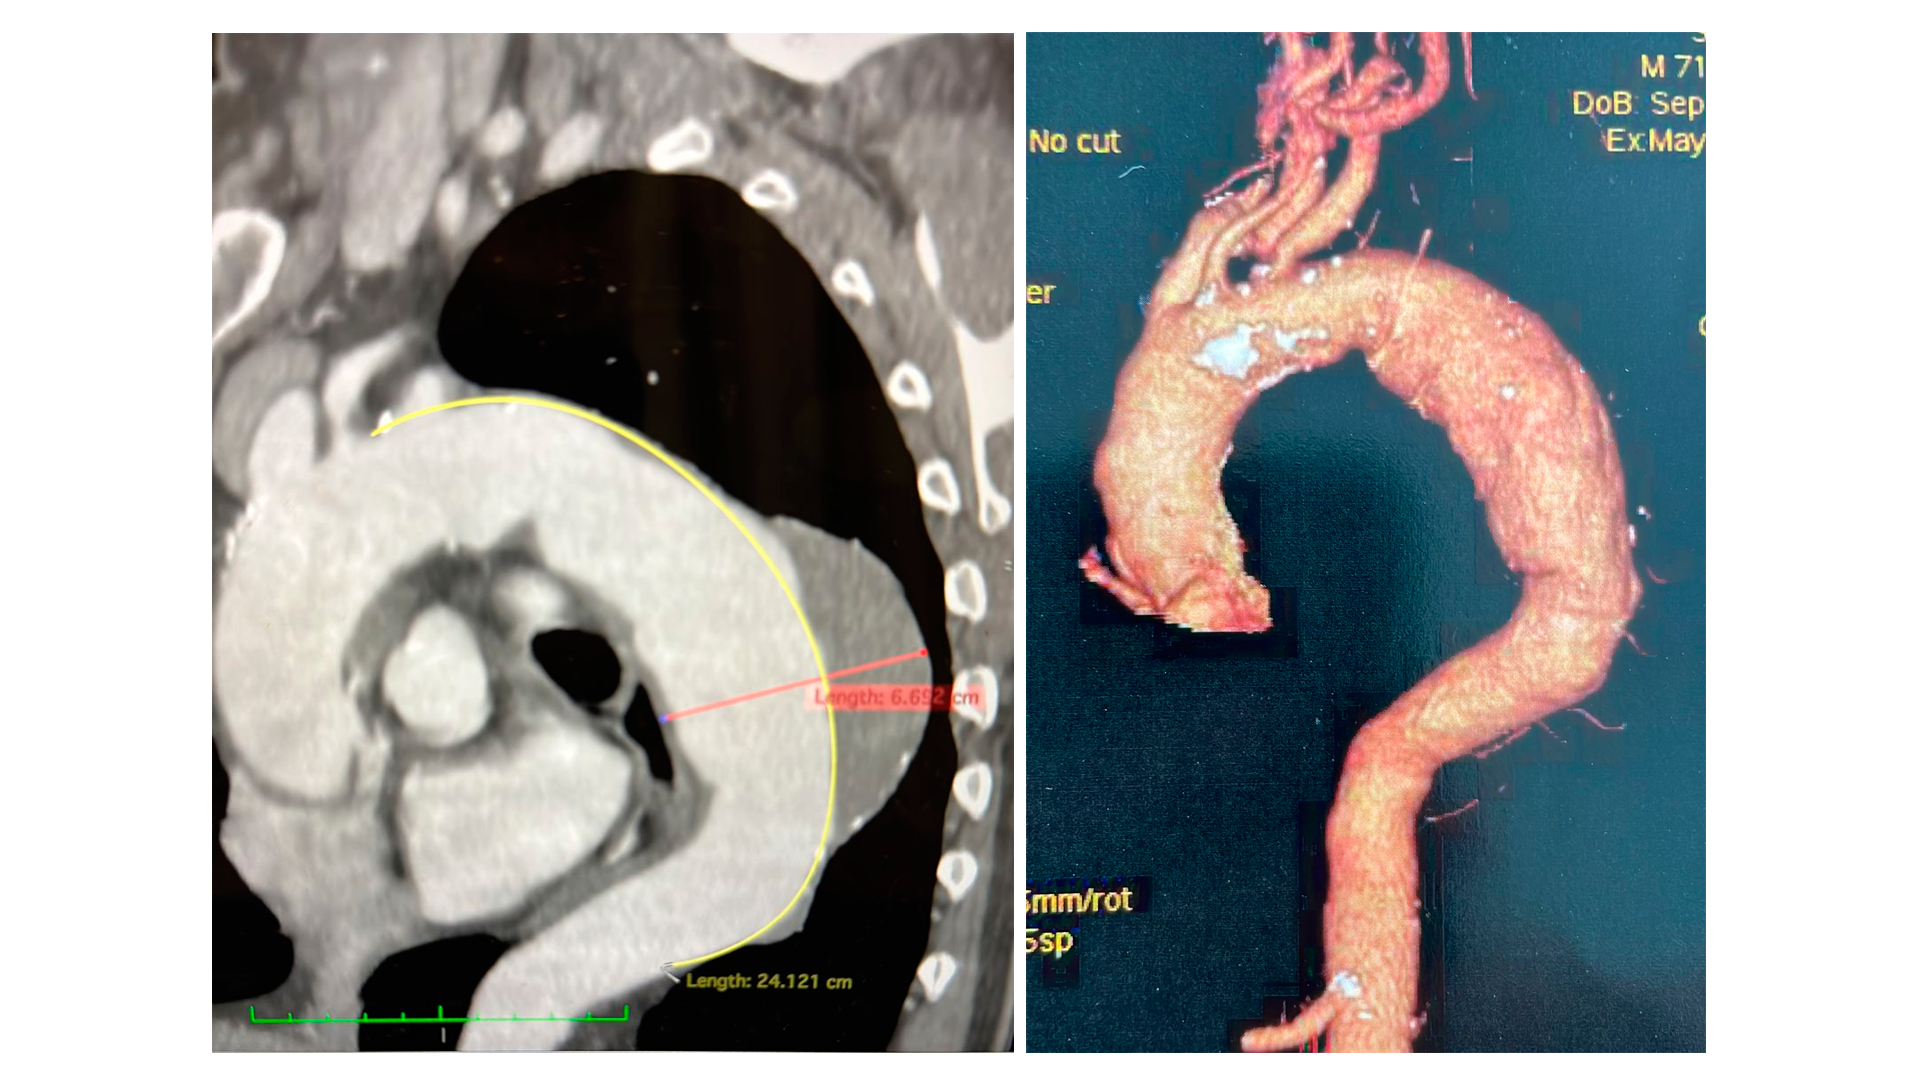

Um procedimento inédito na Bahia, para tratamento de um aneurisma de aorta torácica com prótese ramificada, acaba de ser realizado com sucesso na Santa Casa de Misericórdia de Itabuna. O beneficiado foi um paciente hipertenso, de 71 anos. O quadro de saúde do idoso iniciou com dores nas costas e tórax há três meses, e piorou nas últimas semanas, o que aumentou o risco do rompimento da artéria aorta, o que seria fatal.

O paciente foi submetido a uma cirurgia minimante invasiva (pequeno corte na virilha) com utilização de endoprótese na aorta torácica para normalizar o fluxo de sangue e evitar o agravamento do aneurisma. A cirurgia com uso da prótese ramificada foi feita na unidade de Hemodinâmica da Santa Casa de Itabuna, por uma equipe comandada pelos médicos Luiz Felipe Brandão e André Brito, cirurgiões vasculares e endovasculares.

A cirurgia, conforme o médico Luiz Felipe Brandão, foi realizada depois que exames preliminares apontaram aneurisma de aorta torácica (descendente) e úlceras na parede posterior. “Foi feita investigação para afastar outras possíveis causas e, como o quadro de dor persistiu, ocorreu a internação na Unidade de Terapia Intensiva (UTI) do Hospital Calixto Midlej Filho. Após nova tomografia ficou constatado aumento do aneurisma”, conta.